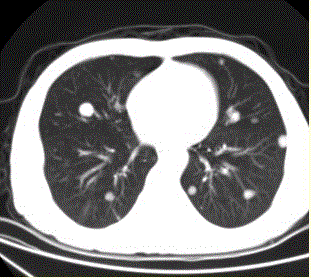

问题 患者男,45岁,因肝硬化、肝癌行肝移植术后6个月,咳嗽2周,来院复查。CR及CT影像如下图。 对于转移瘤和原发癌的关系,描述正确的有

选项 A.肺内转移最多的原发瘤为肝癌 B.原发支气管肺癌可转移到同侧和对侧 C.乳腺癌肺转移可通过血行和淋巴途径,还可经胸膜播散 D.睾丸精原细胞瘤的肺和淋巴结转移灶密度较低 E.中枢神经系统肿瘤易发生肺内转移 F.脑转移瘤中最常见的原发肿瘤为肺癌

答案 BCDE

解析 BCDE